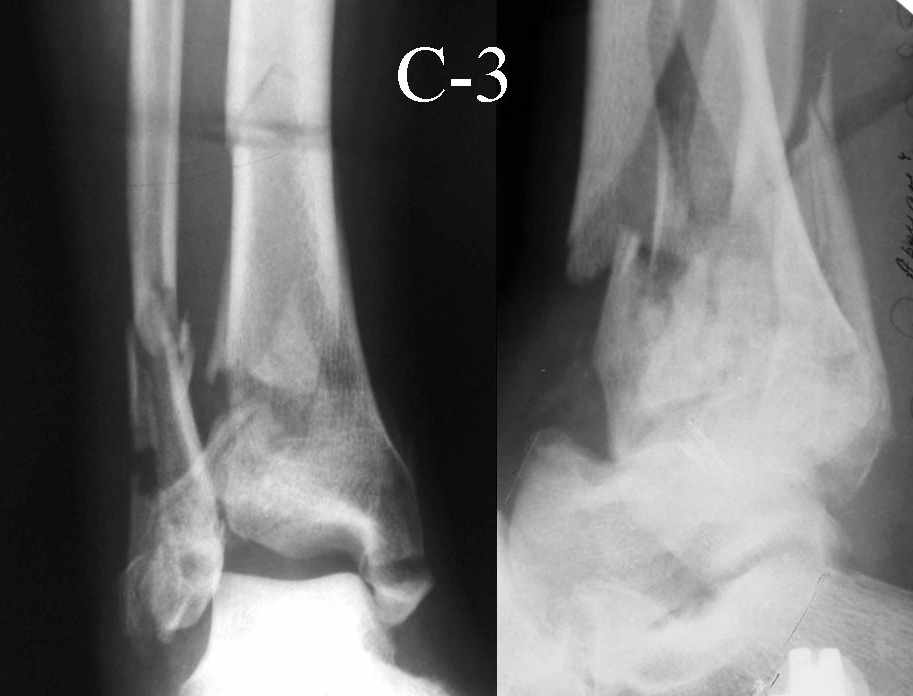

Это типичный перелом пилона, который надп лечить только открыто.Извини те что опоздал к обсуждению, но даже если вы уже оперировали больного по Илизарову это даже лучше.Посылаю картинки.

На рентгенограммах типичный перелом пилона по типу С-3. есть опыт до 100 открытых опреаций у нас в клинике. 20 примерно в год. Принцип один -все внутрисуставные переломы нуждаются в открытой репозиции и внутренней стабильной фиксации. При поступлении КТ не надо, так как получается только нагромождение костей. Истинной картины нет. Главное восстановить длину малоберцовой кости - это ключ к успеху. При поступлении меньше всего надо думать о сосудистых расстройствах, т.к. сама операция и репозиция даже сначала частичная даёт улучшение сосудитых нарушений. Причём очень быстро. Операция в 2этапа. При поступлении доступ позади наружной лодыжки, причём обязательно. После этого репозиция малоберцовой кости и фиксация пластиной 1/3 трубки под винт 3,5. Дренаж и любой аппарат наружной фиксации. Затем после спадения отёка на 5-7-10 день аппрат снимается и дугообразный разрез спереди от медиальной лодыжки 10-12 см. Главной чтобы расстояние между 1 и вторым разрезом было не меньше 7-8 см. Тогда не будет некрозов лоскутов. Таранная кость используется как матрица на неё укладываются отломки и фиксируются пицами. Ренг-контроль. Отломки лежат все отдельно, но ничего не высыпется. При переломах С-3 всегда нужна костная пластика (из крыла). Фиксация пластиной лист клевера простой или LCP. Гипс не нужен. Дренаж до 48 часов. Операция длится 3-4 часа обязательно без жгута. Посылаю примерно такой же случай.